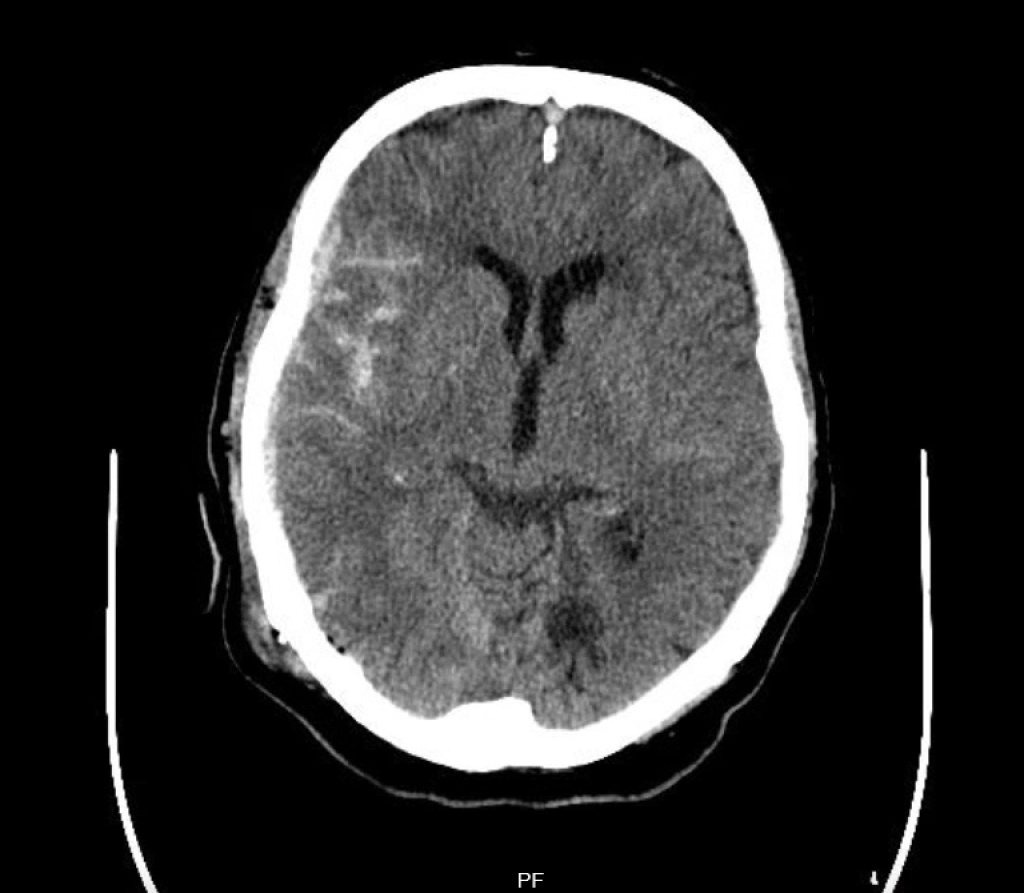

Kontusionsblutungen

Kontusionsblutungen und traumatische Subarachnoidalblutungen (SAB) entstehen durch Einriss parenchymaler, bzw. subarachnoidaler Gefäße. Sie sind immer Ausdruck eines schwereren Schädel-Hirn-Traumas, die größeren Blutungen entstehen dabei typischerweise am contre coup, also kontralateral zur Traumaseite und -stelle, dem coup. Auch Kalotten- und Felsenbeinfrakturen kommen bei Kontusionsblutungen und traumatischen SAB häufiger vor als bei den oft im Rahmen von Bagatelltraumen entstehenden Subduralhämatomen.

Bei Kontusionsblutungen gibt es – wie bei den akuten Subduralhämatomen – relativ klare OP-Indikationen. Indiziert ist eine Hämatomentlastung wenn das Blutungsvolumen mehr als 50 Kubikzentimeter oder der intrakranielle Druck > 20 mmHg beträgt oder eine Mittellinien-Verlagerung > 5 mm oder eine GCS von 6 bis 8 besteht. Gerade große oder im Verlauf „aufblühende“ Kontusionsblutungen gehen mit einer schlechten Prognose einher.